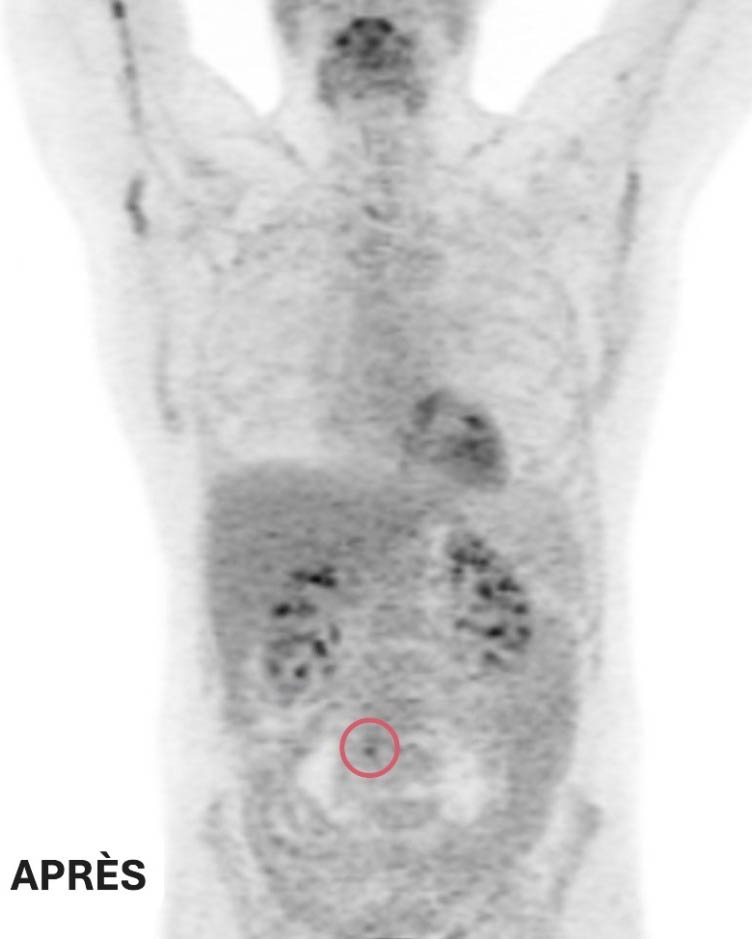

La réponse de Ted au traitement est extraordinaire. Les examens de tomodensitométrie de suivi montrent que les deux petites masses ont complètement disparu et que la grosse tumeur abdominale a rétréci jusqu’à devenir plus petite qu’un petit pois. Compte tenu de la nature agressive du lymphome à double impact, l’équipe de soins de Ted recommande une courte série de séances de radiothérapie pour éliminer toute cellule cancéreuse restante, une mesure préventive visant à réduire le risque de récidive.

Clichés d’imagerie médicale avant et après ses traitements : deux des trois tumeurs de Ted ont complétement disparu. La troisième est maintenant de la taille d’un petit pois – Ted répond très bien au traitement suivi à L’Hôpital d’Ottawa.